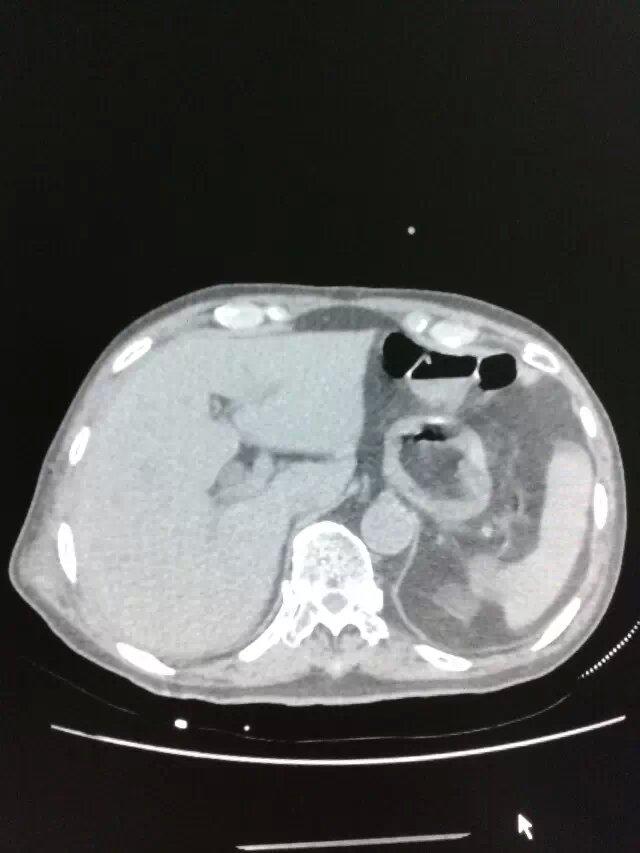

CT49865:胆囊是什么病变?

女,56岁,胆囊是什么病变?

胆囊结石性胆囊炎

胆囊息肉?

建议结合彩超

胆囊占位?胆囊结石 胆总管扩张,建议增强扫描

胆囊炎、胆囊结石。

胆总管结石伴胆总管扩张。

胆囊结石,胆囊炎,胆囊占位?